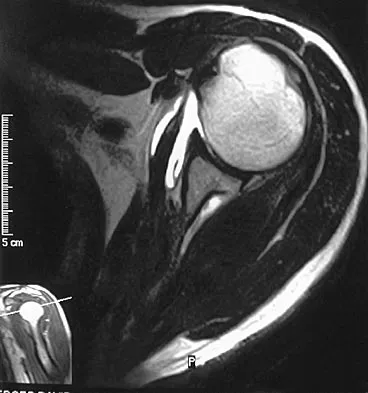

Question 76

A 47-year-old man has acute right shoulder pain after falling off a ladder. The MRI scan shown in Figure 9 reveals

Explanation